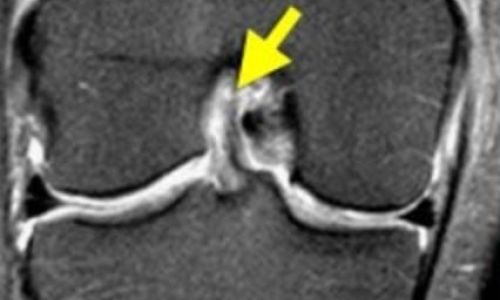

Η διάγνωση γίνεται με λεπτομερή κλινική εξέταση του τραυματισμένου γόνατος ενώ παράλληλα η επιβεβαίωση της διάγνωσης γίνεται με διενέργεια μαγνητικής τομογραφίας γόνατος.

Αποτελεί μια από τις συχνές αθλητικές κακώσεις, συχνότερα στις γυναίκες. Προκαλεί οίδημα (αίμαρθρο) καθώς και αστάθεια (πρόσθια και στροφική) γόνατος.